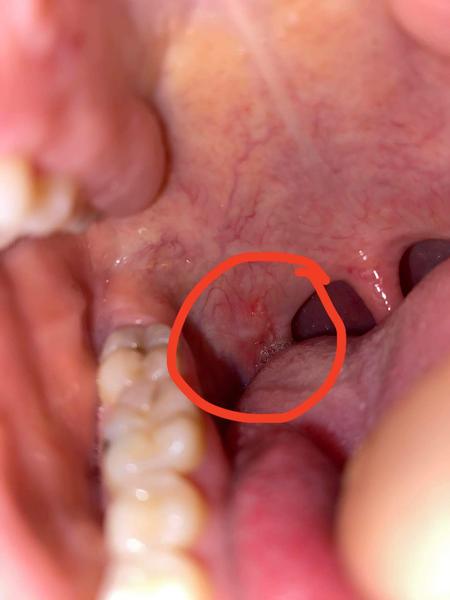

Ahojte, čo môžem mat toto v hrdle ?

@jankak055 ja myslím všzadu take to červené je to taká hrčka. Dnes som začala kloktat slabú vodu. Mám pocit aj že mám zapálene hrdlo len moja lekárka ma dovolenku a neviem či to mám riešiť urgent alebo počkať.

@oliolijanka no mna práveže extra nič neboli, trosku hrdlo ale to je nič. Len tá Hrčka ma trosku znepokojuje.

@jankak055 takú hrčku ste mali v hrdle ? Ja sa strašne bojím či to neni niečo vážne

@jankak055 no hovorím mna to neboli trosku cítim hrdlo ktoré je zapálene ale konkrétne toto ma neboli vôbec 🙂

@dankako aj mne na pohľad ale čo som mala niekedy afty tak tie ma bolelo toto ma vôbec neboli ani na dotyk 🙂